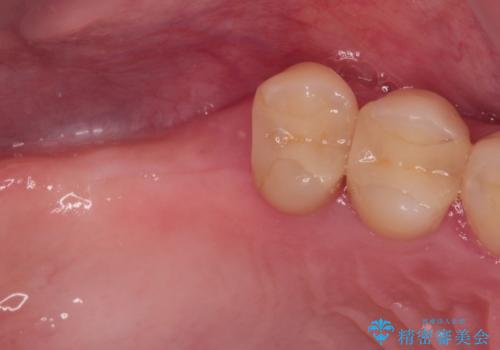

- かかりつけ医にて歯周病治療の名目で治療を行っていたものの、治療プランが明確でないままにインプラント処置を行うとことに疑問を感じ、来院された患者様です。

かかりつけ医では、歯周病治療は終了したため、抜歯を行った右上奥歯にインプラント埋入を行うとの案内があったそうです。

自他共に認める、非常に色白の患者様であったため、黄ばんだ歯の色を白くすることを希望されており、歯周病治療の該当部位に限らず、全顎的にオールセラミッククラウンにて補綴治療を行うこととしました。